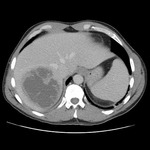

Abscesso hepático: tomografia computadorizada (TC) mostrando um abscesso hepático (7 cm x 5 cm) em um homem de 46 anos de idade que apresentou febre, fadiga e tosse

Do acervo de imagens radiológicas do Massachusetts General Hospital

Abscesso hepático: tomografia computadorizada (TC) (vista coronal) mostrando abscesso hepático em um homem de 46 anos de idade que apresentava febre, fadiga e tosse